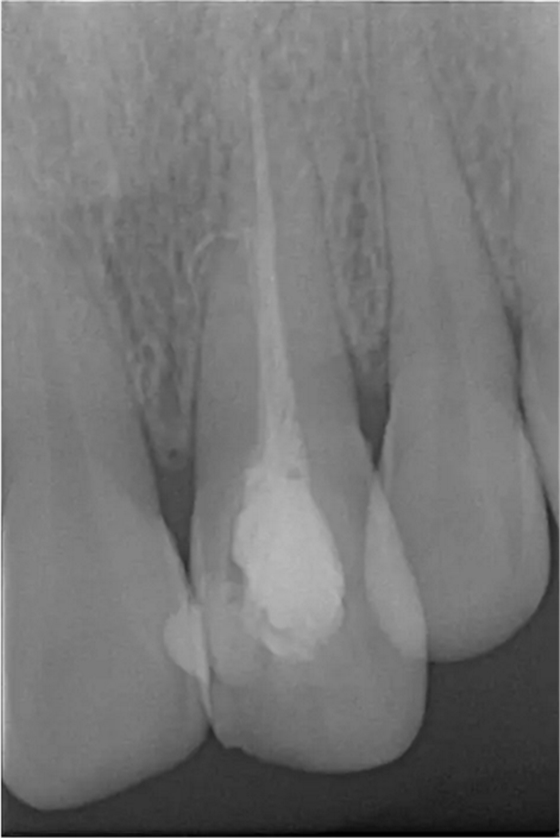

患者女,年齡35左右,牙位21,根管治療曾經(jīng)歷過外院四到五次等不同地方的處理,還是不能咬硬物,會有酸、軟、痛的情況出現(xiàn),偶有自發(fā)疼痛,2016年9月初,轉(zhuǎn)診至我處治療21。術(shù)前拍片發(fā)現(xiàn)根中部存在側(cè)穿,橡皮障下常規(guī)再治療,隨后減輕了軟和痛的情況。因為側(cè)穿,牙周膜受到牙膠尖等異物的持續(xù)刺激,酸軟的情況還是持續(xù)存在,所以決定行根尖外科手術(shù),采用MTA修補(bǔ)穿孔點。術(shù)后觀察半年左右,所有癥狀消除后,隨后熱牙膠充填。

術(shù)前診斷片

術(shù)后片

隨訪半年后,癥狀消除,熱牙膠根充